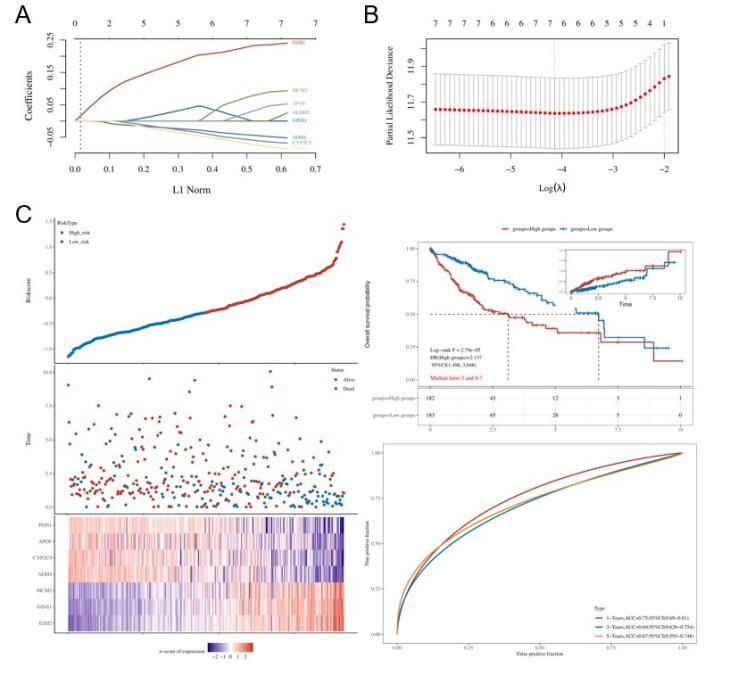

3.4. Construction of a prognostic model using Lasso Cox regression

We used Lasso Cox regression to construct a prognostic model based on selected features. The coefficients of these features were determined by the lambda parameter, with the x-axis representing the lambda values and the y-axis representing the coefficients of the independent variables. The relationship between the partial likelihood deviance and log(λ) was depicted in the Lasso Cox regression plot (Figure 8 A&B). The formula for the final risk score is:

Riskscore=(0.2155)×EZH2+(0.0222)×GINS1+(0.0538)×MCM2+(−0.0376)×ADH4+(−0.0503)×CYP2C9+(0.0049)×APOF+(−0.0593)×PON1

The performance of this model was evaluated using Kaplan-Meier (KM) survival curves, where the risk groups were compared using the log-rank test. A hazard ratio (HR) greater than 1 indicated that the model was a risk factor, while an HR less than 1 indicated a protective model. The median survival time and 95% CI were also determined for groups classified as high-risk and low-risk. According to the ROC curve analysis, the model exhibited significant predictive strength, with the AUC value reflecting robust predictive performance. Our risk score model presents the model’s effectiveness (Figure 8C).